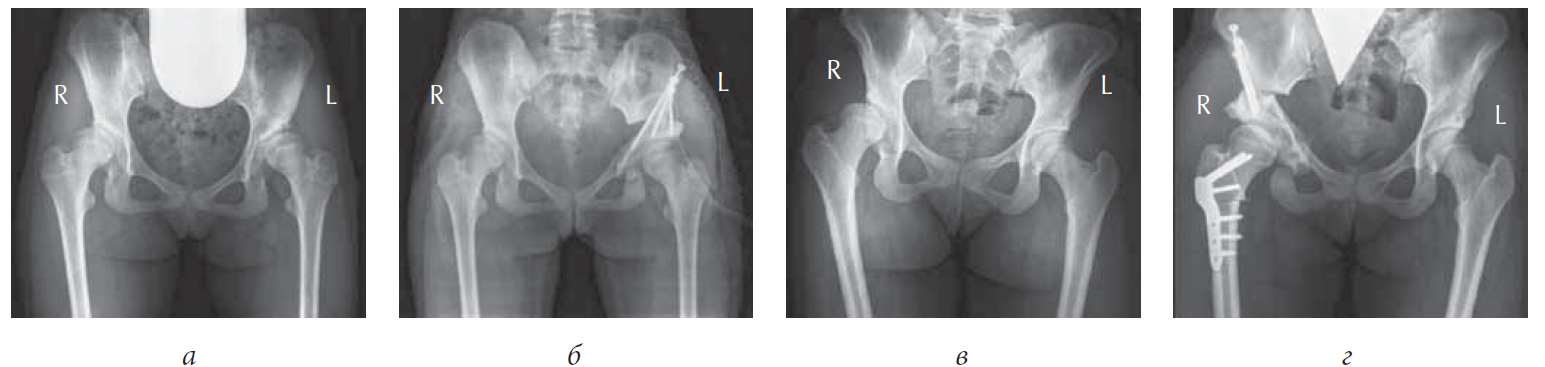

Between 2015 and 2017, we reviewed the results of surgical and regenerative treatment of 40 children (100%) with DKA at different stages. The patients comprised 27 girls (67.5%) and 13 boys (32.5%) aged 13–18 years (total 54 joints). Bilateral pathology was observed in 14 patients (35%). After a comprehensive examination, 15 patients (37.5%) were diagnosed with DKA stage I, 15 (37.5%) with stage IIa, and 10 (25%) with stage IIb. An informed consent was obtained from all patients to participate in the study, to process personal data, to examine and perform surgical intervention. All 40 patients (100%) underwent transposition of the cotyloid cavity after triple osteotomy of the pelvis, alone or in combination with femur osteotomy (Fig. 1). Of note, surgery was performed based on a technique developed in the Department of Hip Joint Pathology (Turner Scientific and Research Institute for Children’s Orthopedics, Saint Petersburg, Russia) from the external-lateral access. In addition, clinical, radial, and electrophysiological research methods were used to assess the anatomical and functional state of the affected hip joint. The clinical examination comprised goniometry, limb length measurement, and gait evaluation. Radiation methods facilitated complex X-ray assessments based on the commonly used indicators (e.g., the angles of Wiberg and Sharp, front cover, inclination of the cavity in the sagittal plane and cervical–diaphyseal and that of the antetorsion, thickness of the cavity bottom, lateral and cranial displacement of the femoral head, and coefficient of the bone coverage) and assessed the severity and dynamics of DDC. In EMNG and EMG studies, the state of the nervous and muscular systems was determined before surgery, followed by evaluation and analysis of the data obtained. In the ENMG study of the femoral, tibial, and peroneal nerves, nerve conductivity was assessed from both sides, including the state of myoneural apparatus of the lower extremities and the dependence of the severity of the deviation of neurophysiological indices of the normal ones. For a comprehensive assessment of the functional condition of the hip joint, all patients were asked to complete the questionnaire of the modified Harris Hip Score scale, signifying the functional condition of the hip joint, and that of the scale developed at the Turner Scientific and Research Institute for Children’s Orthopedics, which characterizes the violations in the typical life of adolescents to a greater extent. The data obtained during this study were processed using the Statistica for Windows (version 6.0) program.

Fig. 1. Radiography of the hip joints in direct projection of patients in the treatment and control groups: a — Patient K., 14 years old, diagnosed with bilateral DKA of stage II, before surgery radiograph; b — Patient K., 14 years old, after transposition of the cotyloid cavity following triple osteotomy of the pelvis on the left. Osteosynthesis of fragments with malleolar screws is seen; c — Patient S., 17 years old, diagnosed with right-sided DKA stage IIa, before surgery; d — patient S., 17 years old, after transposition of the cotyloid cavity following triple osteotomy in combination with corrective osteotomy of the right femur. Osteosynthesis of pelvic fragments with malleolar screws and femur with a plate with angular stability (LCP pediatric hip plate) is seen